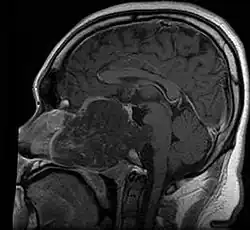

• Skull base:

• May be intracranial or extracranial, with mass effect symptoms depending on location

• Headaches and/or facial pain are common

• Pituitary insufficiency, hemianopsia/diplopia, cranial nerve deficits, nasal stuffiness.

Skull Base

• Hannover; 2007 (Germany) PMID 17695386 -- "Chordomas of the skull base: surgical management and outcome." (Samii A, J Neurosurg. 2007 Aug;107(2):319-24.)

• Retrospective. 49 patients. Transethmoidal approach 36%, pterional 23%, retrosigmoid 23%.

• Outcome: GTR 49%, subtotal resection 51%. Initial surgery GTR 78%. 5-year OS 65%, 10-year OS 39%